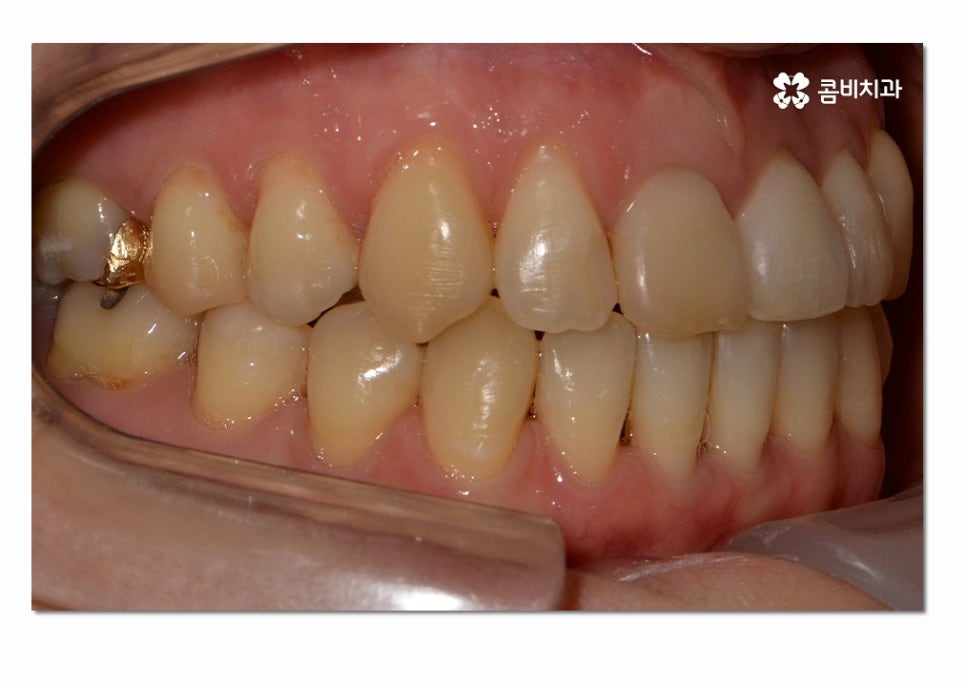

이렇게 옆면으로 보면 교합이 정상적으로 잘 맞물리지 않고

음식물을 골고루 씹어야 하는 어금니가 제대로

맞닿아 있지 않아서 불편함을 느끼게 될 수 있는데요.

치료 경과에 따라서 윗니가 아랫니를 덥게 되는 정상적인

교합 상태로 치열이 변화하는 것을 보실 수 있는데요.